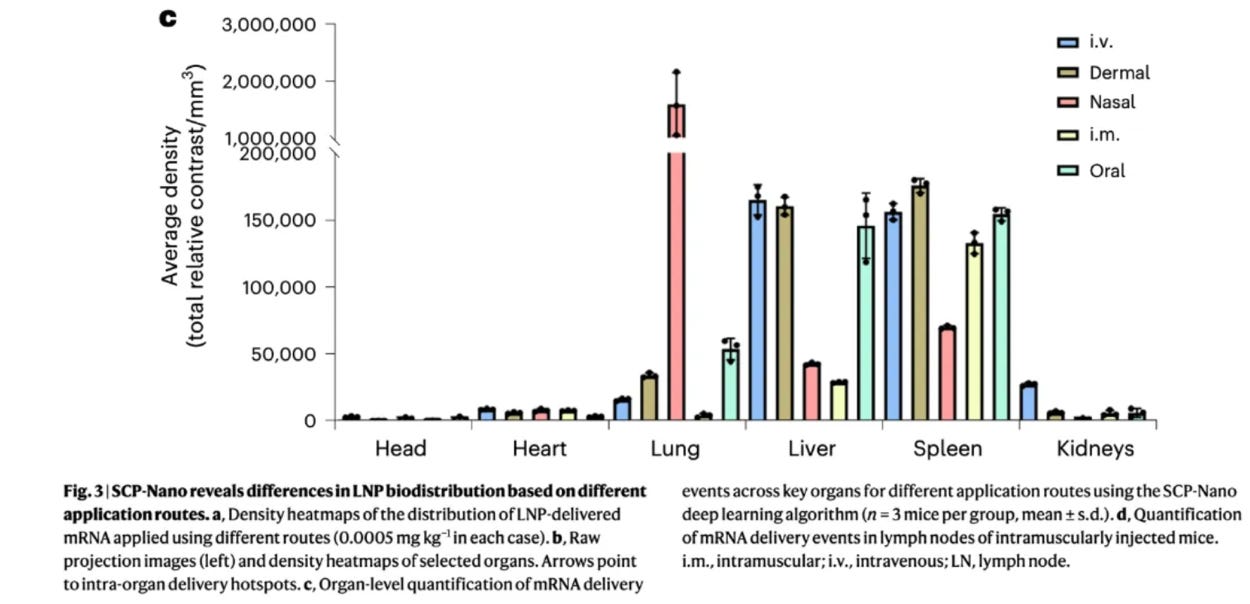

The peer-reviewed study published yesterday in the prestigious Nature Biotechology, titled “Nanocarrier imaging at single-cell resolution across entire mouse bodies with deep learning.” It had forty authors. There’s safety in numbers. They cautiously avoided criticizing the covid shots directly, but the implications were unavoidable.

This study investigated lipid nanoparticles (LNPs), which are the tiny globs of fake fat that deliver mRNA into cells. They tracked the LNPs’ distribution and effects throughout the body—which they found far beyond the injection site. The researchers found that even at very low doses, LNPs wander far afield and worse, they accumulate in unintended organs, triggering immune disregulation and metabolic disturbances.

The study’s carefully documented conclusion upended the government’s original claims the mRNA vaccines would remain “localized at the injection site” (i.e. that they’d quickly and harmlessly dissolve in your shoulder). The findings also provided a plausible explanation for what causes serious known side effects like myocarditis.

These findings aren’t altogether new. They align with earlier findings from a widely ignored 2022 Japanese biodistribution study. The difference now, though, is these scientists used cutting-edge imaging technology to track LNPs in mice, and they used A.I. to analyze very complex data sets (such as systemic effects with multiple variables) and for modeling simulations at various LNP dosages.

Take, for instance, the long-promised vision of using mRNA to deliver customized cancer cures. The concept involves encoding the mRNA with some protein from your specific cancer, in theory prompting the body to mount a targeted immune response. But so long as the treatment relies on lipid nanoparticles (LNPs) to deliver its mRNA payload, this study suggests a potentially catastrophic risk: the cancer protein could unintentionally transfect major off-target organs like the heart, liver, kidneys, and spleen, potentially spreading cancerous material throughout the body while simultaneously disrupting the immune system.